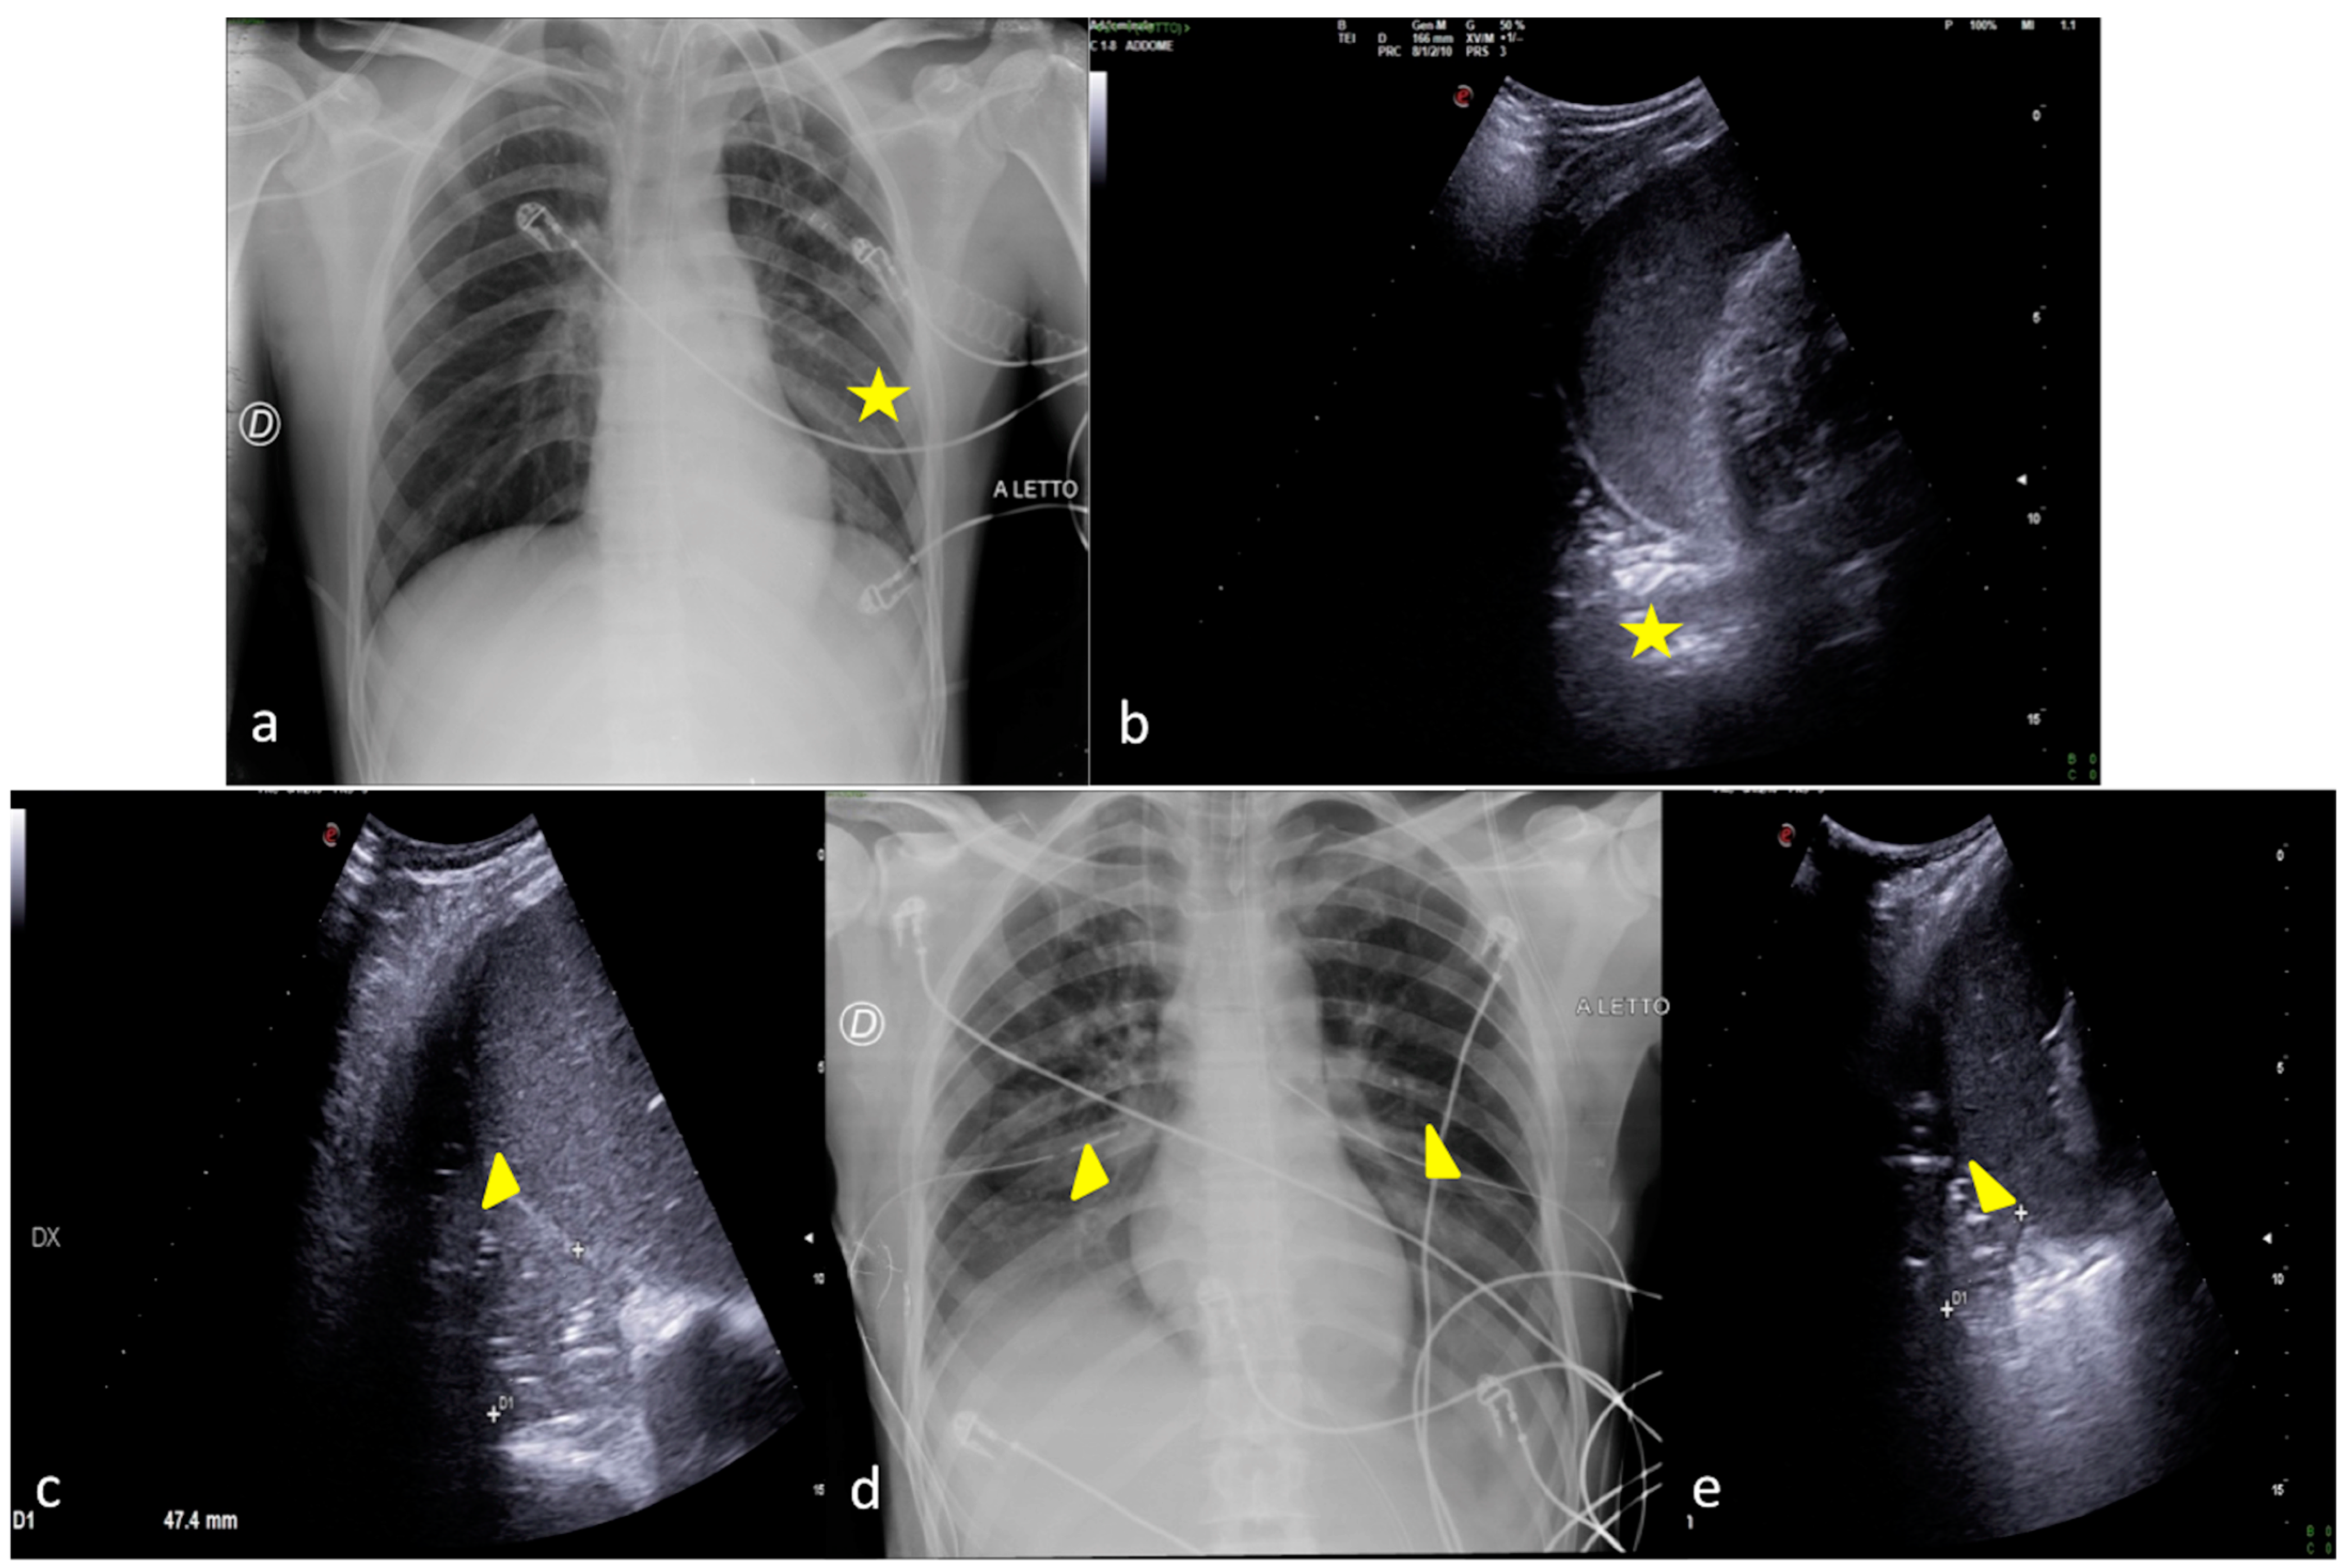

Figure 8.

A 26-year-old male patient admitted to the ICU for a comatose state related to high-energy trauma due to a car accident. Bedside CXR (a,c) and LUS (b). (a) The CXR on the day of admission into the ICU showed normal lung expansion with no evidence of parenchymal change. (b) LSU was performed after 24 h endotracheal intubation with the onset of a respiratory worsening and showed an inhomogeneous area of mixed hypoechogenic change at the basis of the left lung (b, arrowhead) with some hyperechogenic spots suggestive of consolidation with an air bronchogram (b, arrow). (c) The CXR confirmed the LUS findings showing an area of reduced diaphony in the basal left field that was considered the manifestation of parenchymal consolidation (c, arrowhead). The clinical scenario and imaging findings were suggestive of phlogistic bronchopneumonia.

Figure 9.

A 67-year-old male patient referred to the ICU after major trauma by a fall from a height. Bedside CXR (a) and LUS (b,c). (a) The CXR showed bilateral pulmonary opacities associated with pleural effusion (a, arrowheads). (b,c) Bilateral minimal pleural fluid was also confirmed by LUS (b,c, arrows) both on the right (b) and on the left (c) sides; lung consolidation was also visible (b,c, asterisks).

Figure 10.

A 54-year-old male patient in respiratory failure. CT scan (a), CXR (b), and LUS (c). (a) The axial CT scan of the chest showed a parenchymal consolidation area with the air–fluid level in the basal segments of the right inferior pulmonary lobe suggestive of a pleural empyema (a, arrow). (b) The subsequent CXR control revealed a basal right-side decreased parenchymal transparency consistent with a persistent amount of the empyematous effusion (b, arrow). (c) LUS follow-up showed a better quantification of the residual fluid amount, with an inhomogeneous content of echogenic substance in suspension (c, arrow) and also confirmed the correct position of the surgical drainage tube (c, arrowhead).